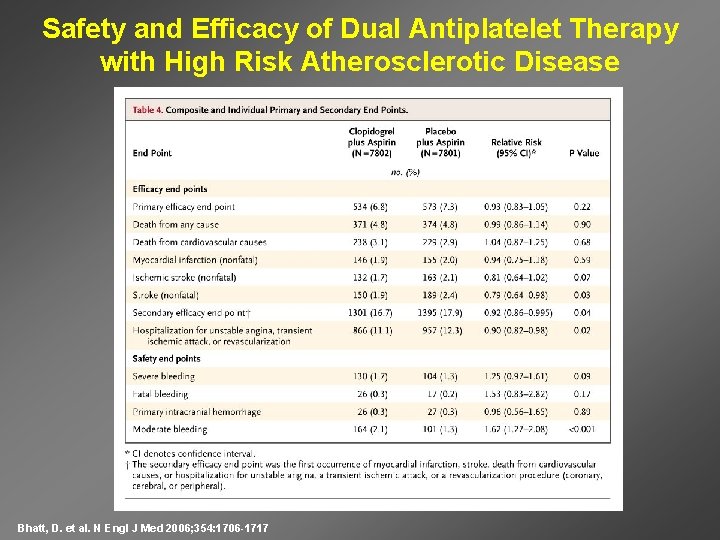

Safety and Efficacy of Dual Antiplatelet Therapy with High Risk Atherosclerotic Disease Bhatt, D. et al. N Engl J Med 2006; 354: 1706 -1717